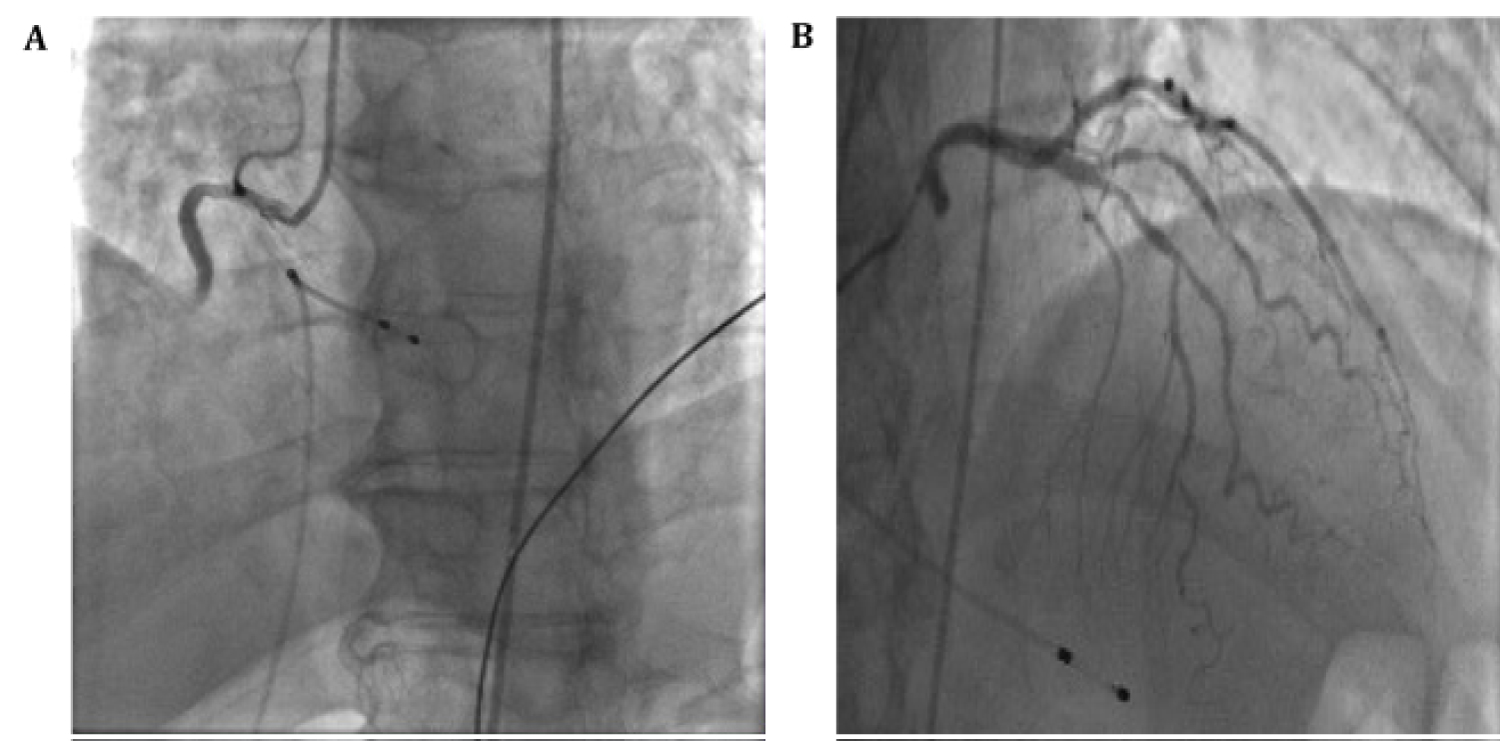

Cardiac catheterization showed 100% mid right coronary artery (RCA) stenosis as well as moderate disease in the left anterior descending artery (LAD) (Figure 2 and Video 1). The decision was made to perform PCI of the RCA lesion; however, despite thrombectomy, balloon angioplasty, stenting, and intracoronary vasodilators and glycoprotein IIb/IIIa inhibitors, there was TIMI flow 0 (Figure 3, Video 2 and Video 3). Intravascular ultrasound was performed to assess stent expansion and the distal coronary vessel. The epicardial vessel visualized distal to the stent was patent with mild atherosclerosis, with no visible edge dissection. It was determined the distal coronary bed could not regain flow due to persistent microvascular thrombus and occlusion. An intra-aortic balloon pump was placed prior to transfer to intensive care unit and an eptifibatide infusion was continued for 18 hours.

Figure 3: (A) Coronary angiography of PCI; (B) Coronary angiography with continued poor distal flow after thrombectomy, PCI and intracoronary vasodilators. View Figure 3